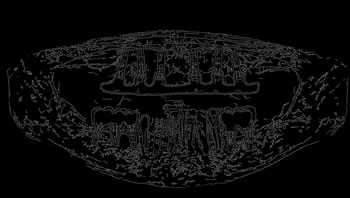

Determining ROI

For each image, after the annotation of the teeth, the buccal region was also annotated, covering the whole region delineated by the contour of the jaws. This process was carried out in view of preserving the area containing all the teeth (objects of interest). Finally, the region of interest (ROI) was determined by multiplying the values of the pixel array elements, representing the original panoramic X-ray image, by its corresponding binary matrix, resulting from the process of oral annotation. Figure 5 illustrates the whole process to determine the ROI of the images.